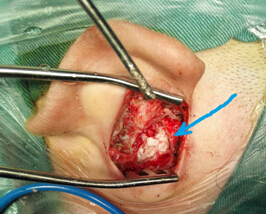

3.術(shù)前CT2 4.術(shù)中術(shù)腔中的巨大膽脂瘤

5.膽脂瘤清除后的乳突鼓室腔 6.術(shù)后傷口愈合